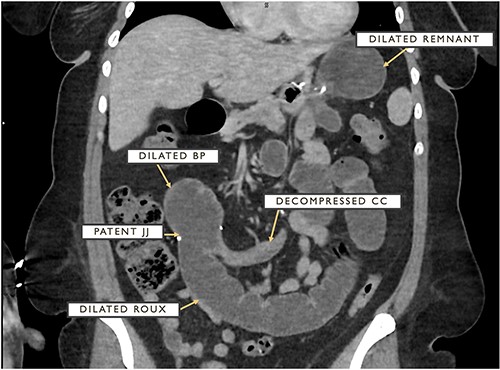

The patient is a 34-year-old female with a pre-operative BMI of 40 mg/m2 who presented with acute onset (<24 hours) epigastric pain, nausea and dry heaves approximately 1 month following an uncomplicated laparoscopic retrogastric/retrocolic RNYGB with concomitant hiatal hernia repair and cholecystectomy. On arrival, she was hemodynamically stable with a softly distended and tender but non-peritoneal upper abdomen. Lab work including WBC and lactate were unremarkable. Computed tomography (CT) imaging revealed a dilated remnant stomach, BP limb and roux limb with a patent JJ anastomosis but a decompressed CC with concern for an internal hernia (Fig. 1).

CT cross-section demonstrating dilated remnant stomach, BP limb and roux limb as well as a patent JJ anastomosis with a distally decompressed CC.